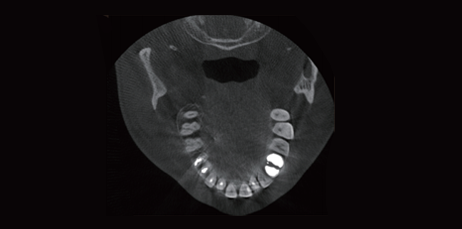

AI + Tooth Perspectives

Tooth Perspectives: 3D reconstruction of a single tooth is carried out to clearly display the shape of the tooth, the form of the pulp cavity, and the 3D structure of the root canal and gums.